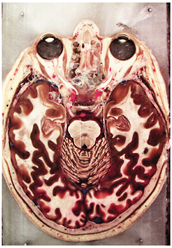

Table 2, Table 3, Table 4 and Table 5 present the results obtained through the multi-objective optimization image enhancement approach. Specifically, Table 2 and Table 3 show the results for natural images, while Table 4 and Table 5 display medical images. The tables are organized as follows: the first and second columns list the image names and their corresponding original, unenhanced versions. The third to fifth columns showcase the selected points from the Pareto front, representing the maximum contrast, knee point, and maximum detail, in that order. The final column illustrates the obtained Pareto front through the optimization process, with red, green, and orange points indicating the images that achieved maximum contrast, knee point, and maximum detail, respectively.

Table 4.

Medical image results—1.

As observed in the results, the images extracted from the Pareto front significantly maximize contrast and detail compared to the original images. In all study cases, the original image is dominated by the solutions extracted from the fronts, demonstrating the approach’s effectiveness in improving visual quality. However, the differences among the three enhanced images for each problem require a more detailed analysis.

For medical images, there are instances where differences are more perceptible. For example, in the Medical3 image, the maximum contrast solution makes it difficult to visualize the internal details of the basophil (a white blood cell highlighted in the box), which could result in a less accurate interpretation. In contrast, the knee and maximum detail solutions provide a clearer view of the interior of the white blood cell. Similarly, in the Medical5 image, the maximum contrast solution highlights the hand and arm bone structures. However, the maximum detail image offers a more precise view of the internal structures within the bones (see the highlighted region), which is crucial for a more detailed evaluation. Another notable example is the Medical8 image, where the maximum detail solution offers a more detailed view of the internal structure of the eosinophil (another type of white blood cell). However, the maximum contrast image improves the visibility of red blood cells. As shown in the yellow box, this solution reveals a red blood cell that is nearly imperceptible in the other solutions. An interesting case is the Medical6 image, where only a few non-dominated solutions are present on the Pareto front. Despite the similarities among the preferred solutions, the nodules are much more perceptible in the enhanced images than in the original image, as observed in the highlighted region.